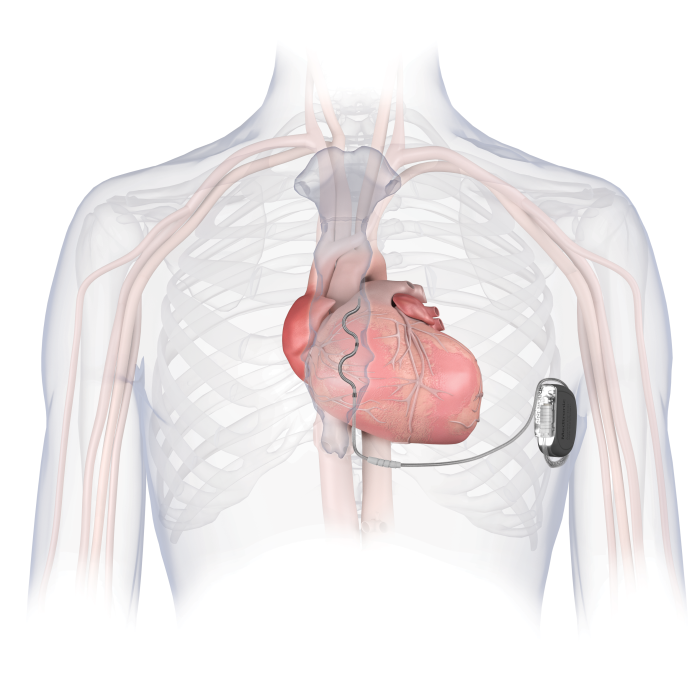

EV-ICD血管外植入式心律转复除颤器作为全球创新的植入式除颤技术,区别于现有的经静脉ICD和皮下ICD系统,采用创新的胸骨下除颤电极放置,避免了血管内并发症以及从心脏和血管中拔除电极导线相关的风险。

Aurora EV-ICD™ 结合了现有经静脉和皮下ICD系统的优势,既不需要将电极植入心脏和血管内,同时实现了完整的除颤复律和抗心动过速起搏(ATP)治疗功能,装置体积小,预估使用寿命长达11.7年,为患者减少了未来设备更换的次数和经济负担。同时兼容1.5T 和3.0T MRI 全身磁共振扫描,术后更加美观舒适,不影响患者日常生活,是室性心律失常治疗及心脏性猝死防治领域的又一大技术突破,为患者提供了全新心脏性猝死预防和治疗方案。